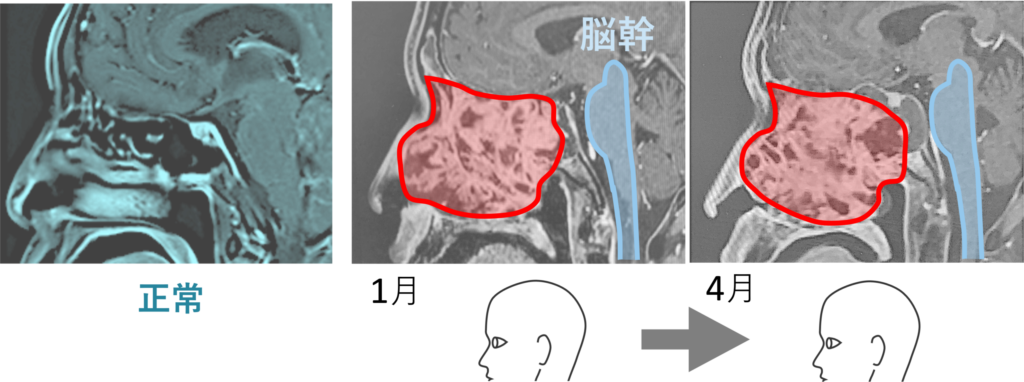

10月、画像診断でガンのコアに大きな空洞が映し出された。しかも巨大化しつつあるかに見えた全体像が縮小している。つまり真ん中に空洞ができては、その空洞が押しつぶされ小さくなり、それを繰り返しながら全体像が小さくなったのである。

そうである。1月・4月・7月までの画像の変化はほとんどなく、若干大きくなったかに見える。一見、治療は効いていないかに見える。しかし、画像には映らないガンの「中身」の変化があったのだ。すなわち、1月はカチカチに硬かったガンがだんだんと、コア (芯) の部分から柔らかくなってきていたのだ。

下に置いた画像 (7月→10月) を見ていただくと分かるのだが、この血塊はガン中心部が崩れて排出されたものである。中心部が抜け落ちて、やがて少しずつガンの全体が縮小し、聴神経を圧迫しなくなったのである。ガン中心部から崩壊が始まったのだ。

ガン中心部が抜け落ちてできた空洞が、押されて小さくなっていくにつれて、ガン全体の輪郭も小さくなっていった。血塊が出ていないのに、7/20の血塊排出から時間を挟んで8/8に目が見えるようになった理由をそのように説明する。

すなわち、7/20血塊排出直後に画像を撮ったならば、その血塊分の空洞ができていたはずである。空洞ができ、ガンの圧力によって空洞が徐々に狭められるとともに、ガン全体のの輪郭が小さくなってきた。そう推測されるのである。

ガン中心部に空洞が出現した。あの血塊排出は、やはりガン排出だったのである。カチカチだったガンが、中心部からドロドロになり、ドロドロのガンを吐き出したのである。

画像でガンの中心部分が抜け落ちているとドクターから言われた。